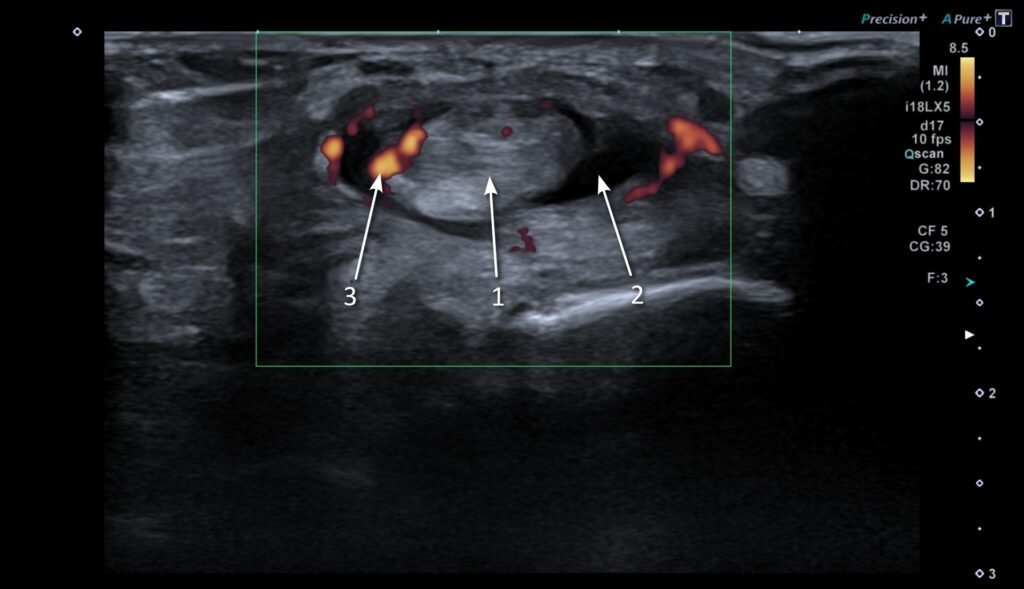

The tendons around the ankle are enveloped by a tendon sheath. This contains a sliver of synovial fluid, a lubricant facilitating the gliding of the tendons during ankle motion. Tenosynovitis is when the tendon sheath itself gets inflamed. On ultrasound, this is seen as a build-up of fluid, thickening and increased blood flow (see Figure 4).